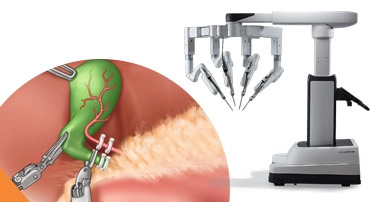

Robotic Heart Surgery in India: Benefits of da Vinci Xi for Complex Cardiac Conditions

Think of your expensive luxury watch; in case there is any defect, if you try to fix the delicate gears present inside the watch with large tools. What will happen? Chances are, even a small movement mistake could cause significant damage.